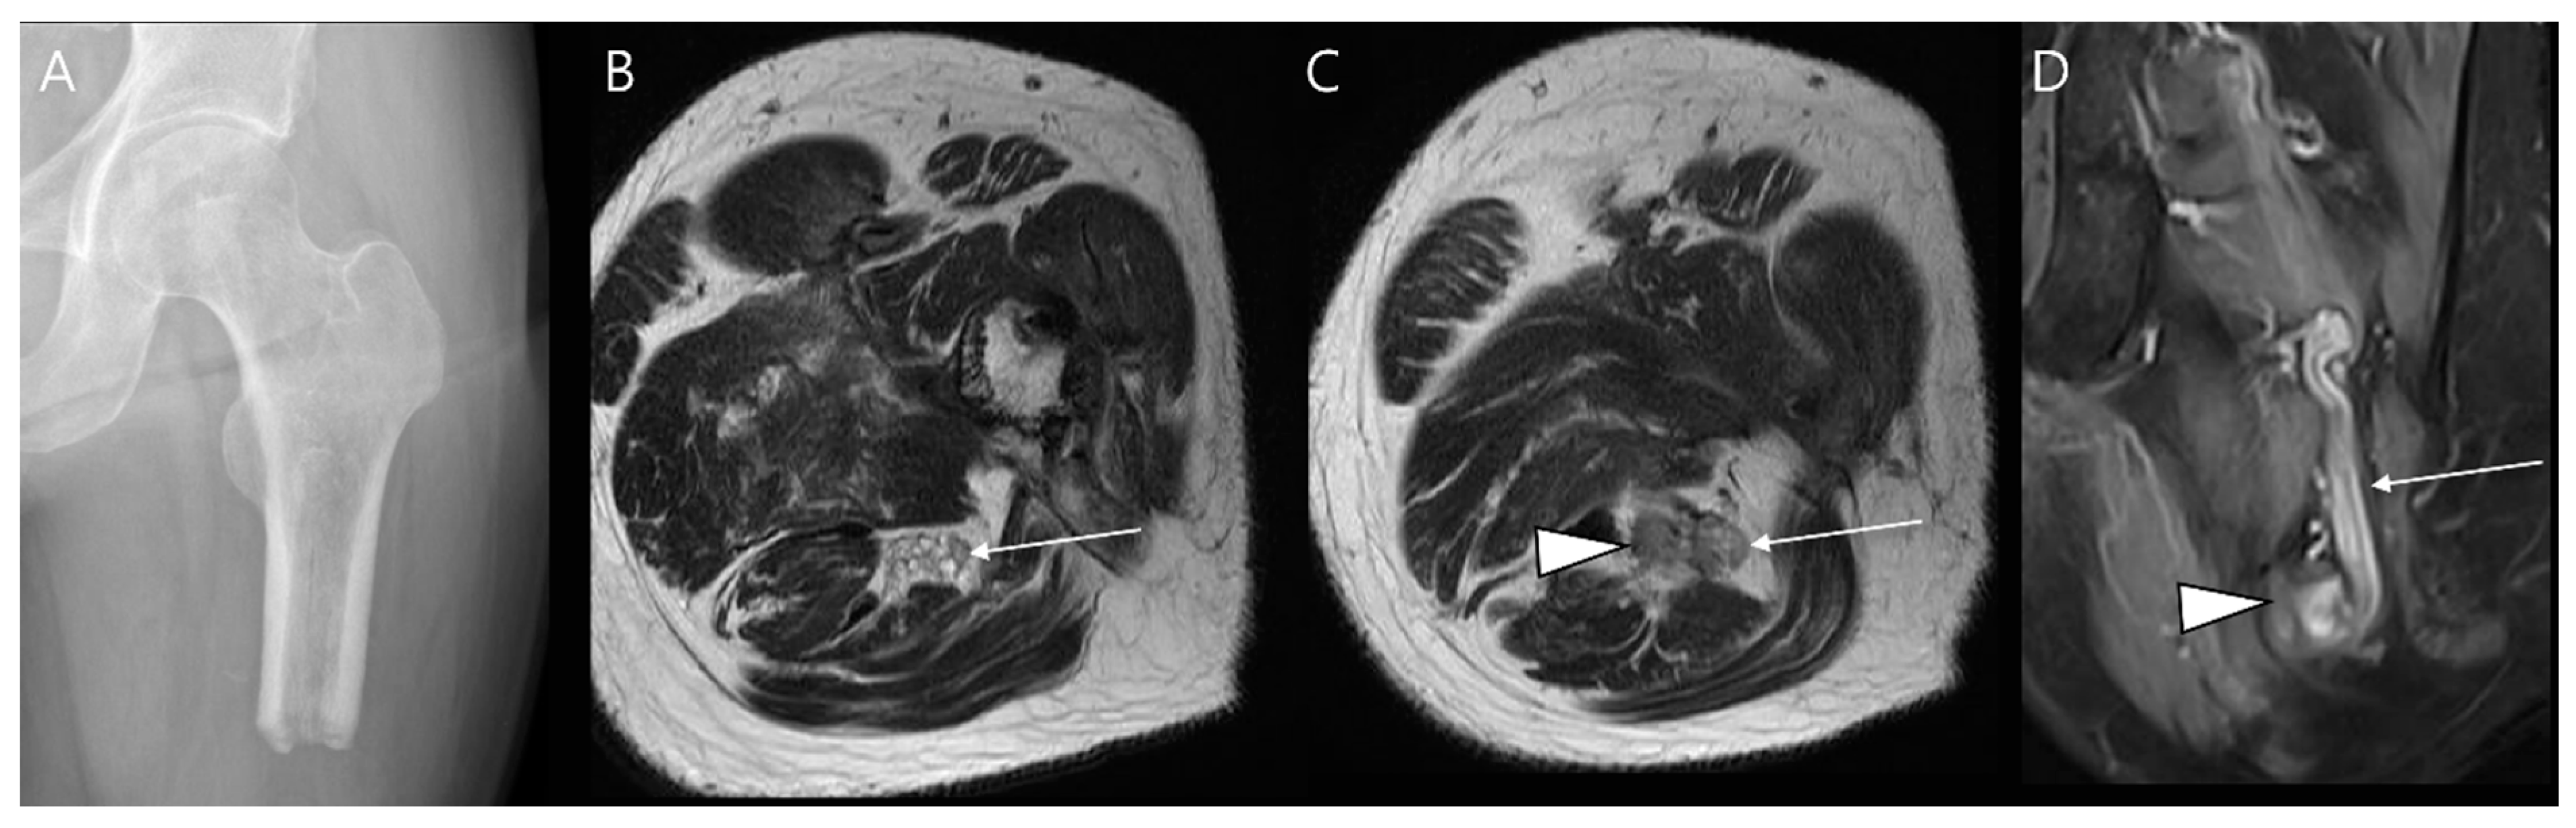

- Noebauer-Huhmann, I.M.; Chaudhary, S.R.; Papakonstantinou, O.; Panotopoulos, J.; Weber, M.A.; Lalam, R.K.; Albtoush, O.M.; Fueger, B.J.; Szomolanyi, P.; Grieser, T.; et al. Soft Tissue Sarcoma Follow-up Imaging: Strategies to Distinguish Post-treatment Changes from Recurrence. Semin. Musculoskelet. Radiol. 2020, 24, 627–644. [Google Scholar] [CrossRef]

- Shapeero, L.G.; De Visschere, P.J.; Verstraete, K.L.; Poffyn, B.; Forsyth, R.; Sys, G.; Uyttendaele, D. Post-treatment complications of soft tissue tumours. Eur. J. Radiol. 2009, 69, 209–221. [Google Scholar] [CrossRef] [PubMed]

- Song, E.H.; Lee, S.Y.; Lee, S.; Jung, J.Y.; Shin, S.H.; Chung, Y.G.; Jung, C.K. Diagnosis of Local Recurrence of Malignant Soft Tissue Tumors after Reconstructive Surgery on MRI. J. Clin. Med. 2023, 12, 4369. [Google Scholar] [CrossRef]